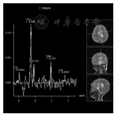

CT检查:左侧脑室体部团块状稍高密度影(图1),CT值约38 HU,大小约32.6 mm(前后径)×28.3 mm(左右径)×29.1 mm(上下径),左侧脑室后角明显扩大。MRI平扫+增强:(1)左侧脑室体部团块状混杂信号,T1WI、T2WI以等高信号为主,其内可见小片状低信号,FLAIR呈等高信号,DWI以高信号为主,增强扫描后肿块中心可见不均匀中等强化,余颅内未见明显异常强化(图2,图3,图4,图5);(2)MRS:肿块内测量NAA/Cr降低,Cho/Cr、Cho/NAA明显升高(图6);(3)头颅MRA未见明显异常;脑电图示轻度异常脑电图。影像检查提示高级别恶性肿瘤性病变,首先考虑间变性室管膜瘤,脉络丛乳头状癌及胚胎性肿瘤不除外。

GG在颅内的影像表现具有多样性,是一种少见的颅内原发性肿瘤,好发于大脑半球的浅表部位,多见于颞叶。影像上主要分为囊性、囊实性、实性3种。囊变和钙化被认为是节细胞胶质瘤的常见表现。Majores等[10]认为囊性病变并壁结节钙化是GG的特征性表现之一。本例发生于左侧脑室前角内,较为罕见,病变以软组织密度/信号为主,内见散在斑片状钙化,没有脑室外GG常见的囊变表现。病变局部与左侧脑室前角壁分界欠清,磁共振DWI呈较高信号,提示弥散受限,多考虑高级别肿瘤;结合MRS示NAA/Cr降低,Cho/Cr明显升高,术前影像首先考虑间变性室管膜瘤,其次考虑脉络丛乳头状癌。幕上室管膜瘤/间变性室管膜瘤分属WHO Ⅱ~Ⅲ级,幕上可位于侧脑室、脑实质或骑跨生长[11],肿瘤内可出现钙化、囊变和出血,密度或信号较为混杂,DWI提示弥散受限时,多考虑间变性室管膜瘤。本例未见明显囊变和出血成分,增强后未呈现室管膜瘤典型的环形强化[12],与室管膜瘤/间变性室管膜瘤不太符合。脉络丛乳头状瘤好发于脑室,尤其是侧脑室内,WHO分Ⅰ~Ⅲ级,Ⅲ级脉络丛乳头状癌具有高级别恶性肿瘤特征性表现:DWI弥散受限、合并出血、钙化、囊变,可突破侧脑室壁侵犯邻近脑实质,也可随脑脊液播散转移[13],因常起源于脉络丛,可分泌脑脊液,示侧脑室扩大,与本例较为相似。不过结合冠状位观察本例病变部分阻塞侧脑室侧孔可能是导致左侧脑室积水主要原因;因肿瘤生长挤压侧脑室壁变形扩大且分界不清,而并非直接侵犯侧脑室壁。此表现影像鉴别尤为重要,本例肿瘤DWI呈现较高信号,提示弥散受限,且MRS提示Cho/Cr明显升高,易与侧脑室好发恶性肿瘤混淆。术后回顾分析图像本例以实性为主伴少量钙化,不伴水肿及周围组织侵犯,发生于孟氏孔附近,符合节细胞胶质瘤良性表现,但考虑到弥散受限以及MRS中Cho/Cr明显升高,笔者认为不除外肿瘤向更高级别演变可能,这需结合临床长期随访,总结经验。